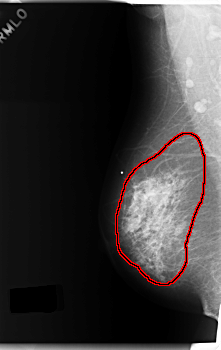

C_0179_1.LEFT_MLO

RIGHT_MLO LINES 5944 PIXELS_PER_LINE 3744 BITS_PER_PIXEL 12 RESOLUTION 50 OVERLAY

FILE: C_0179_1.RIGHT_MLO.OVERLAY

TOTAL_ABNORMALITIES 1

ABNORMALITY 1

LESION_TYPE CALCIFICATION TYPE PLEOMORPHIC DISTRIBUTION REGIONAL

LESION_TYPE MASS SHAPE IRREGULAR MARGINS ILL_DEFINED

ASSESSMENT 5

SUBTLETY 5

PATHOLOGY MALIGNANT

TOTAL_OUTLINES 1

BOUNDARY